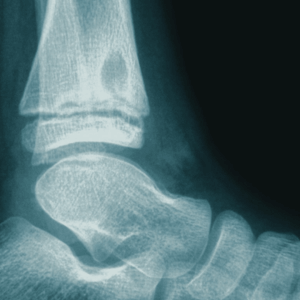

Clubfoot (congenital talipes equinovarus)